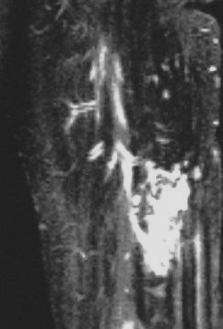

各种静脉畸形的MRI表现:均为治疗困难型

弥漫性静脉畸形